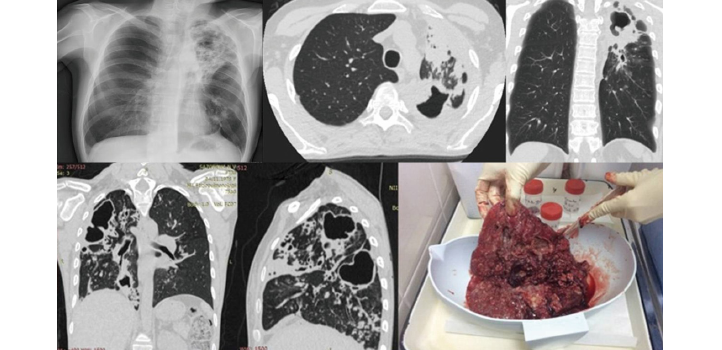

SURGERY FOR MDR TUBERCULOSIS

Surgical resection is an adjunctive intervention for patients with MDR or XDR TB. ... All patients received multidrug regimens preoperatively and postoperatively. The preoperative sputum smears and cultures were positive in 52 patients (72%) and 58 patients (81%), respectively.